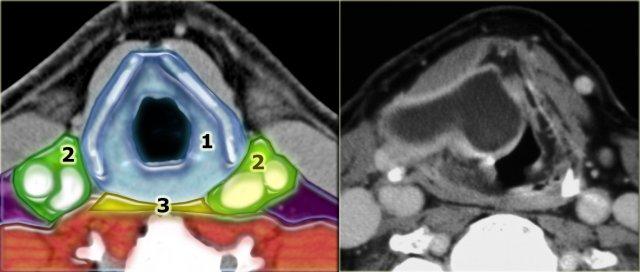

Khoang tạng trải dài từ xương móng đến trung thất trước và không kéo dài vào khoang trên xương móng.

Bên trái là hình ảnh các thành phần bình thường và bệnh lý xuất phát từ khoang tạng.

Lát cắt CT ở mức thanh quản trên thanh môn và sụn giáp.

Phía trước sụn giáp là các cơ dây đai (strap muscles): cơ ức giáp, cơ ức móng, cơ giáp móng và cơ vai móng.

Tất cả các cơ này đều bám vào xương móng và có chức năng hạ thấp xương móng và thanh quản trong quá trình nuốt và nói.

Các cơ này dài và dẹt, có hình dạng tương tự như một chiếc dây đai.